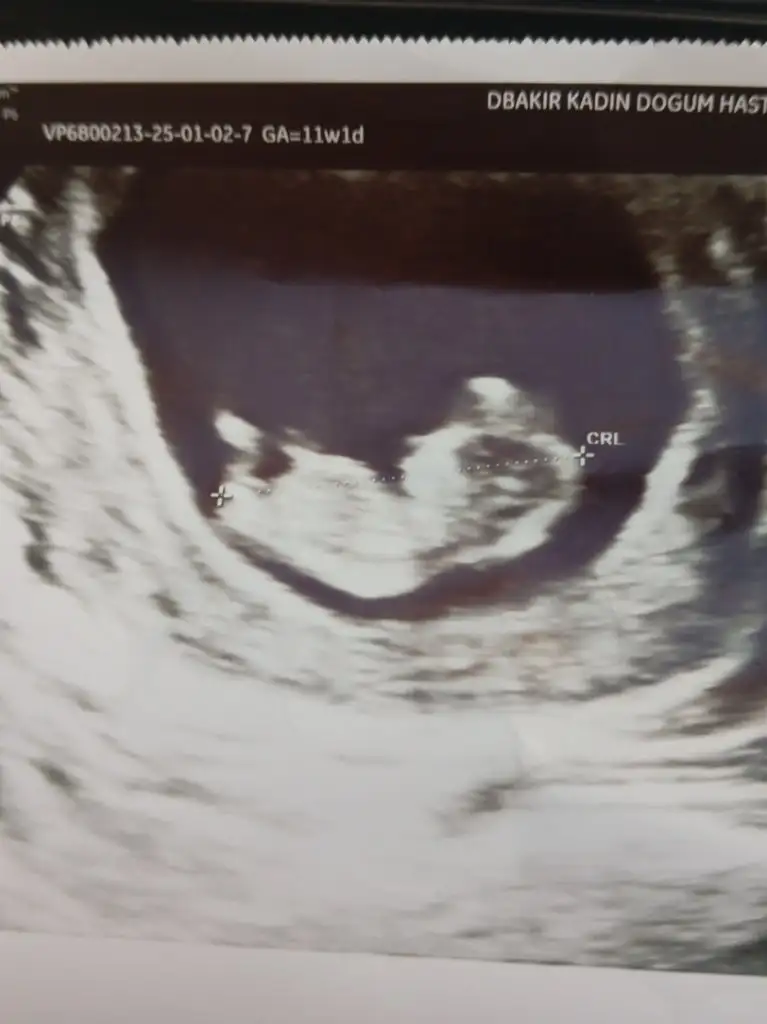

Banana bakarmisiniz

Kızlar bı arkadaş keseye göre tahmin yapıyor ve hep tutuyormuş iki oğlunu da bu şekilde cok yeniyken bile tahmin etmiş...ogullarinda kesesi hep uzunmuş muz gibi...yuvarlak ve yuvarlağa yakın olanlar hep kızdır diyor..ve bayağı emin konusuyor..benimki şişman bı fasulye gibi oo kesin kız görürsün dedi...sizlerin keselerinin şekli nasıldı ve cinsiyet neydi konusalimmi 😊